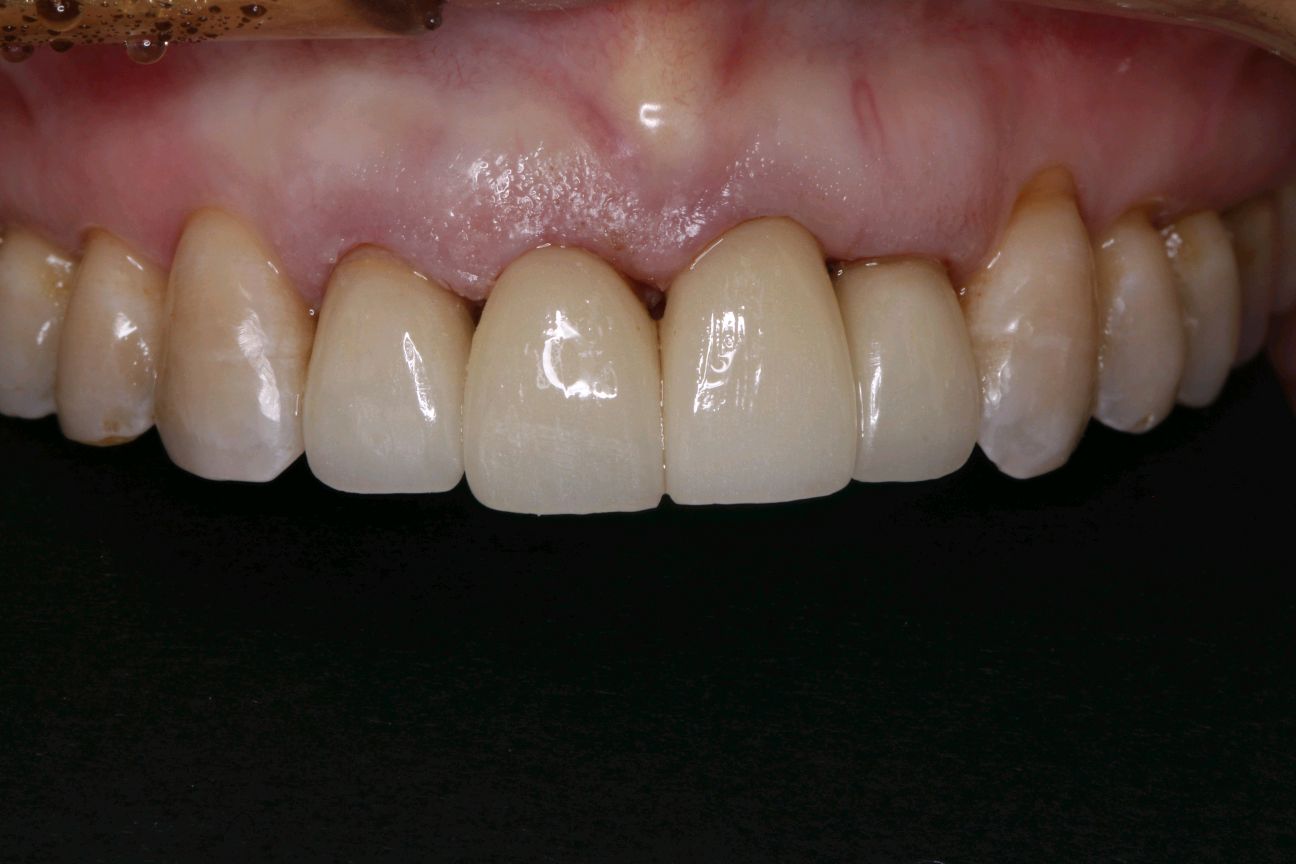

患者女,三十岁,11、12、21,22牙已行根管治疗+烤瓷全冠修复。由于长时间烤瓷牙的佩戴,导致牙龈边缘发黑,边缘不密合,颈缘处牙龈组织出现"黑线"。腭侧部分也出现了崩瓷的现象。对于这种情况,建议患者尽早重新修复,避免二次伤害。患者最终选择重新修复,也给出患者合理的方案,患者选全瓷冠修复,与今日佩戴完毕。边缘密合度良好,形态色泽自然美观,患者满意。

术中